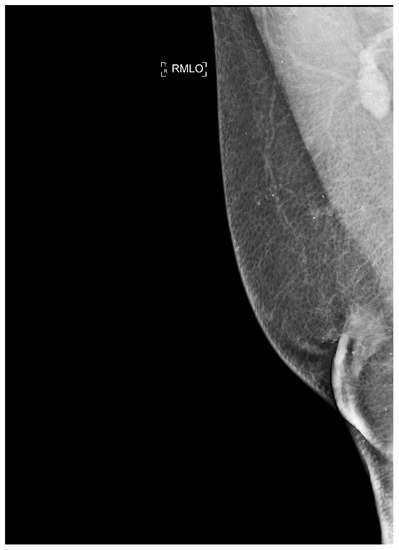

Kim et al. [29] in a study evaluated gender differences regarding the distribution and prevalence of CAC, its relationship to clinical risk factors, and the effect of a high calcium score (≥100) on subsequent initiation of medical therapy by evaluating a court of 542 individuals, of whom 279 were female and 263 were male. The data demonstrated an increasing CAC score with age, regardless of sex. However, women showed significantly lower CAC scores than men in the same age group. The lower CAC scores in women are likely in part indicative of the fact that women have a greater amount of non-calcifying plaque, so-called low-attenuation plaque, than men, indicating that lower CAC scores may actually be related to higher-risk plaque. However, there are also cases, although less frequent, of men with low-attenuation atheromasic plaque (Figure 1). Another interesting finding emerged from the correlation between CAC and clinical risk factors: for both sexes, age had a similar effect on CAC score (OR 1.11 and 1.12, respectively); however, in men, obesity showed a significant effect on CAC score (OR 2.16), while in women, smoking showed a significant effect on CAC score (OR 4.27). This result clearly demonstrated that the traditional clinical risk factors and which women, therefore, share with men actually have different clinical impact in the two genders. Finally, it was investigated how the CAC score result affected the further management of men vs. women with a CAC score ≥100 when adjusted for concurrent coronary CTA findings (moderate to severe lesions vs. non-obstructive lesions) in initiating aspirin and statin therapy [29].

Figure 1.

Male, 39-years-old, patients with history of dyslipidemia, type-1 obesity, and higher level of stress at work. The patient reported a non-anginal chest pain for which an ergometric ECG stress test was performed, and the results were negative. According to the Diamond–Forrester score, the patient was first categorized as a low pre-test probability risk of having CAD. To correctly rule-out CAD, the patients underwent CCTA examination, which showed a severe non-calcific plaque in the distal right coronary artery (white arrowhead).